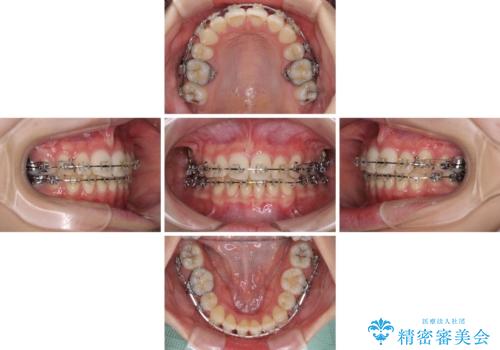

治療途中で転院 抜歯矯正の仕上げ治療

- 地元で抜歯治療を行っている途中、東京へ転職したため治療を継続して欲しいとのことで来院された患者様です。

出っ歯を抜歯矯正にて治療をしていらっしゃいましたが、抜歯スペースが少し残っていたため、閉じて歯列を仕上げていくこととしました。